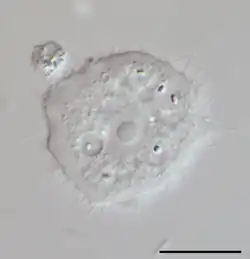

Acanthamoeba est un genre d'amibozoaires, les plus fréquents dans le sol, et aussi fréquemment trouvé dans l'eau douce et d'autres habitats. Les cellules sont petites, typiquement entre 20 et 40 μm de long en fonction des espèces, et peuvent prendre deux formes : une forme dormante, kyste ou une forme active, trophozoïte (aussi nommé végétative). Ces formes leur permettent de se mouvoir, se diviser et se nourrir plus facilement. Cet organisme peut passer d'une forme à l'autre en fonction des conditions environnementales. Si elles sont favorables à sa croissance, le trophozoïte est observé, alors qu'en cas de stress on observera un kyste. Les pseudopodes forment clairement un lobe hémisphérique antérieur, et il y a différentes courtes extensions filiformes au bord du corps. Elles lui donnent une apparence épineuse à laquelle le nom Acanthamoeba se réfère. Les kystes de la plupart des espèces d'Acanthamoeba sont habituellement de types polygonaux et sont fréquemment retrouvés. La plupart des espèces sont des prédateurs naturels des bactéries libres, mais certaines sont des parasites opportunistes qui peuvent causer des infections aux humains et autres animaux.

Les espèces d'Acanthamoeba se distinguent surtout d'après leurs kystes. Ces espèces sont divisées en 12 groupes (du T-1 à T-12), basés sur la séquence ADN du ribosome 18S. Elles incluent les suivantes (celles marquées d'un astérisque sont connues comme causant des infections):